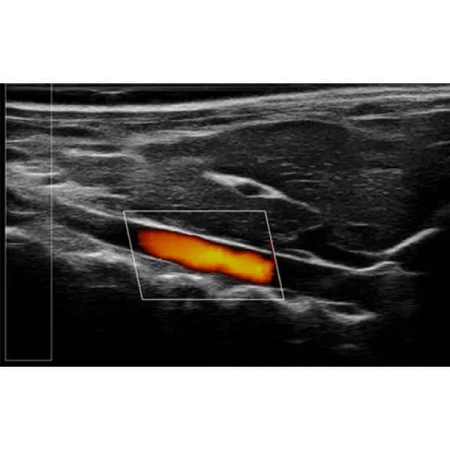

Благодаря неинвазивной и экономичной конструкции RevoSilex идеально подходит для повторных измерений в ходе долгосрочных исследований. Он обеспечивает точный мониторинг структуры, функции и гемодинамики сердца, что делает его незаменимым для исследований сердечно-сосудистых заболеваний и тестирования лекарств. Возможности цветного допплеровского картирования системы еще больше повышают ее полезность при оценке кровотока и выявлении ранних маркеров заболеваний.

Помимо исследований сердечно-сосудистой системы, RevoSilex также широко используется в онкологии и разработке лекарств, где он помогает визуализировать кровоток в опухоли и оценивать терапевтическую эффективность. RevoSilex F30/F60 обеспечивает высококачественную визуализацию в режиме реального времени для ускорения научных исследований в области болезней и генетики.